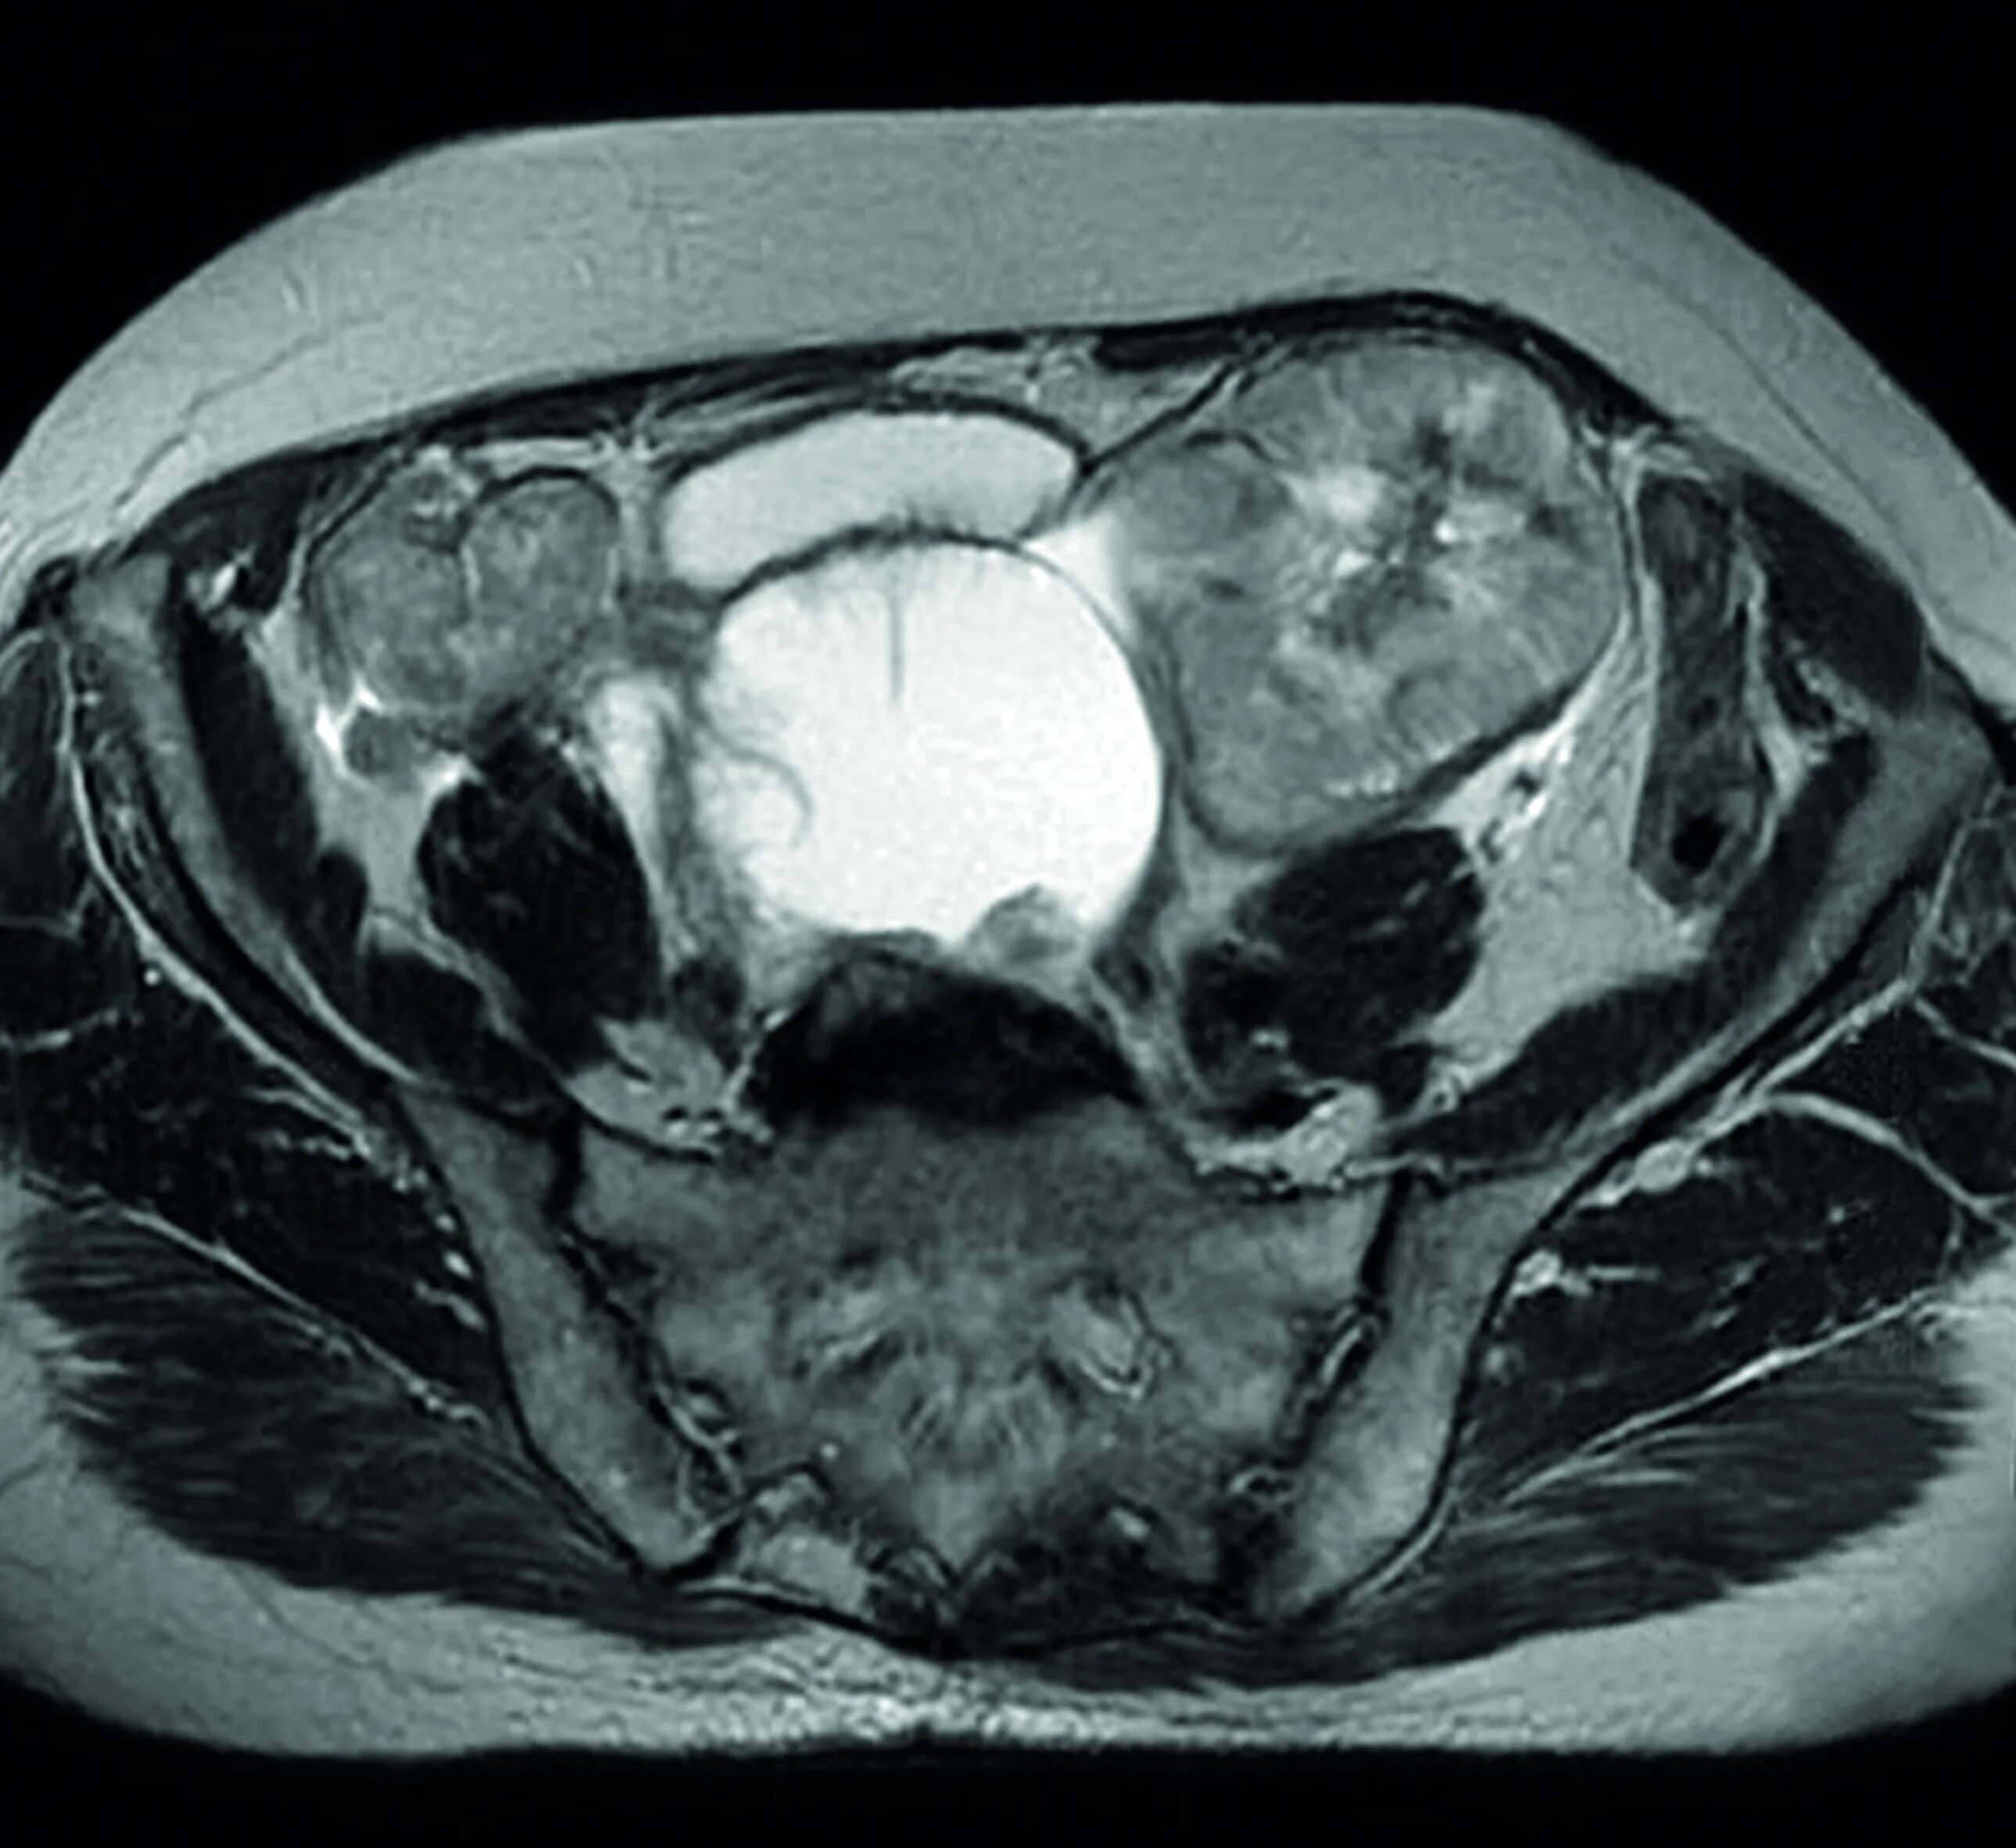

Где можно сделать кт малого таза